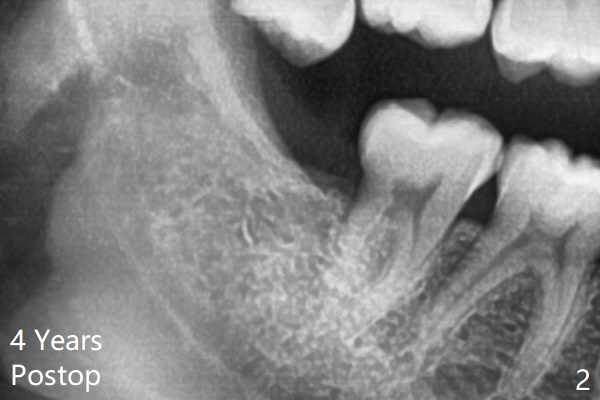

Osteogen plug is placed in the sockets of #17 and 32 post extraction.  The sockets heal 4 years later (Fig.2).